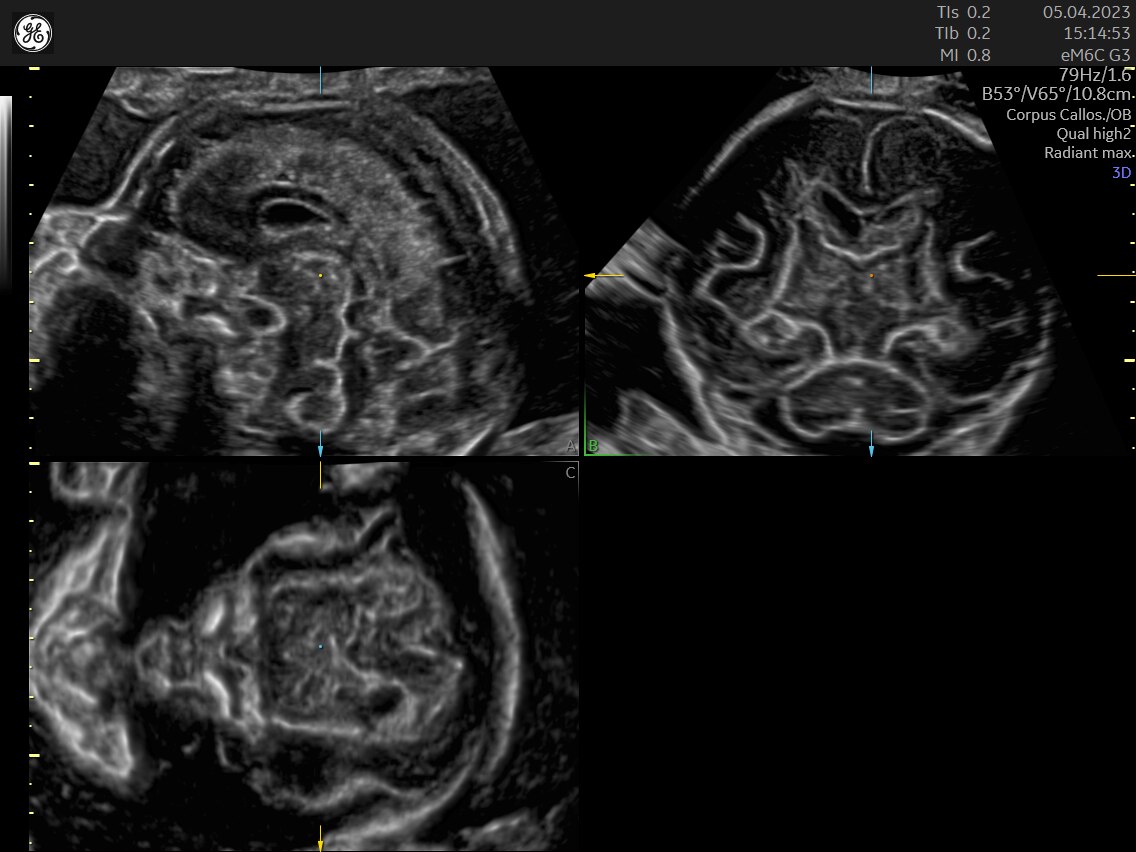

FETAL HEART EVALUATION

Get to the Heart of the Matter

Identifying fetal cardiac abnormalities earlier means you can intervene sooner, plan for delivery, and potentially improve outcomes. The Voluson Expert 22 provides a full solution of progressive tools, to help distinguish the tiniest structures with stunning clarity to provide patient answers faster.